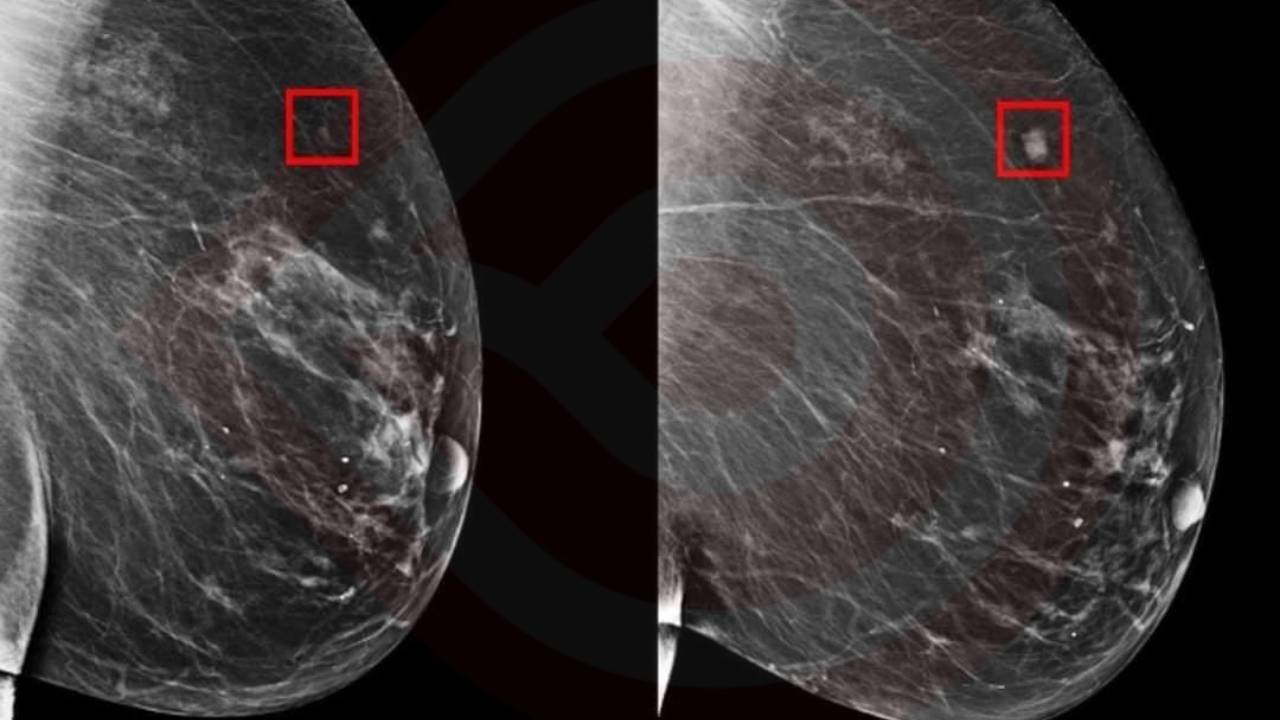

El modelo AsymMirai utiliza la comparación bilateral de los tejidos mamarios izquierdo y derecho, un enfoque que hasta ahora solo se empleaba para detectar la presencia de cáncer, pero no para predecirlo en el futuro. Este método permite identificar diferencias sutiles entre ambos lados y utilizarlas para anticipar el desarrollo del cáncer, con una precisión notable que abarca desde uno hasta cinco años de anticipación.

Además, el hecho de que AsymMirai permita identificar diferencias localizadas en el tejido mamario puede servir como una herramienta adicional para los radiólogos, reduciendo la dependencia excesiva de algoritmos complejos y promoviendo diagnósticos más precisos.